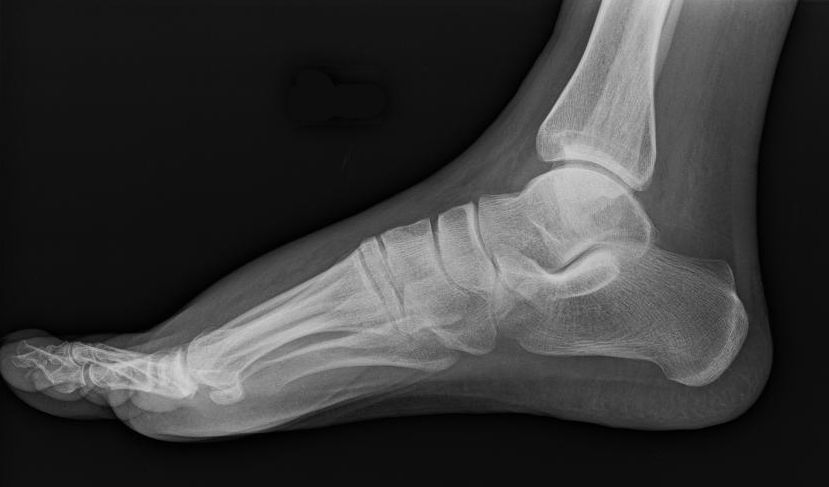

DESCRIPTION — WHAT YOU’RE SEEINGThe first image is an X-ray scan of the human boot — a medical view translated into material. That scan is printed directly onto the boot’s surface, aligning anatomy to form with surgical precision.The skeletal structure of the foot is fully exposed: phalanges, metatarsals, calcaneus, arch. The image continues upward, revealing the tibia and fibula, extending the scan beyond the foot into the lower leg — a complete anatomical read, embedded into a monochrome shell.The boot becomes an interface between body and object. Cold, high-contrast imaging collides with industrial footwear. Clinical data becomes aesthetic. Protection becomes transparency.The result feels illicit and futuristic — medical imaging weaponized into fashion. A post-human artifact where the body is not hidden, but permanently mapped.